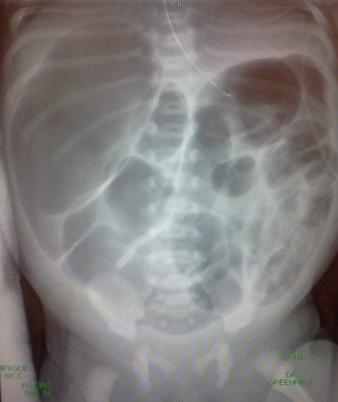

- Start simple - an abdominal radiograph is very helpful in determining next steps.

- The utilization of decubitus films can often help expedite the determination for operative intervention if pneumoperitoneum is found.